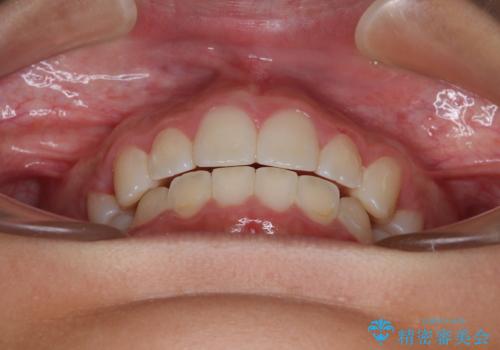

- 口元の突出感で口が閉じにくいとのことで来院された患者様です。

上下左右の第一小臼歯4本を抜歯し、ワイヤー装置での抜歯矯正を行うこととしました。

口元の突出感が解消され、睡眠時の口呼吸が改善されました。